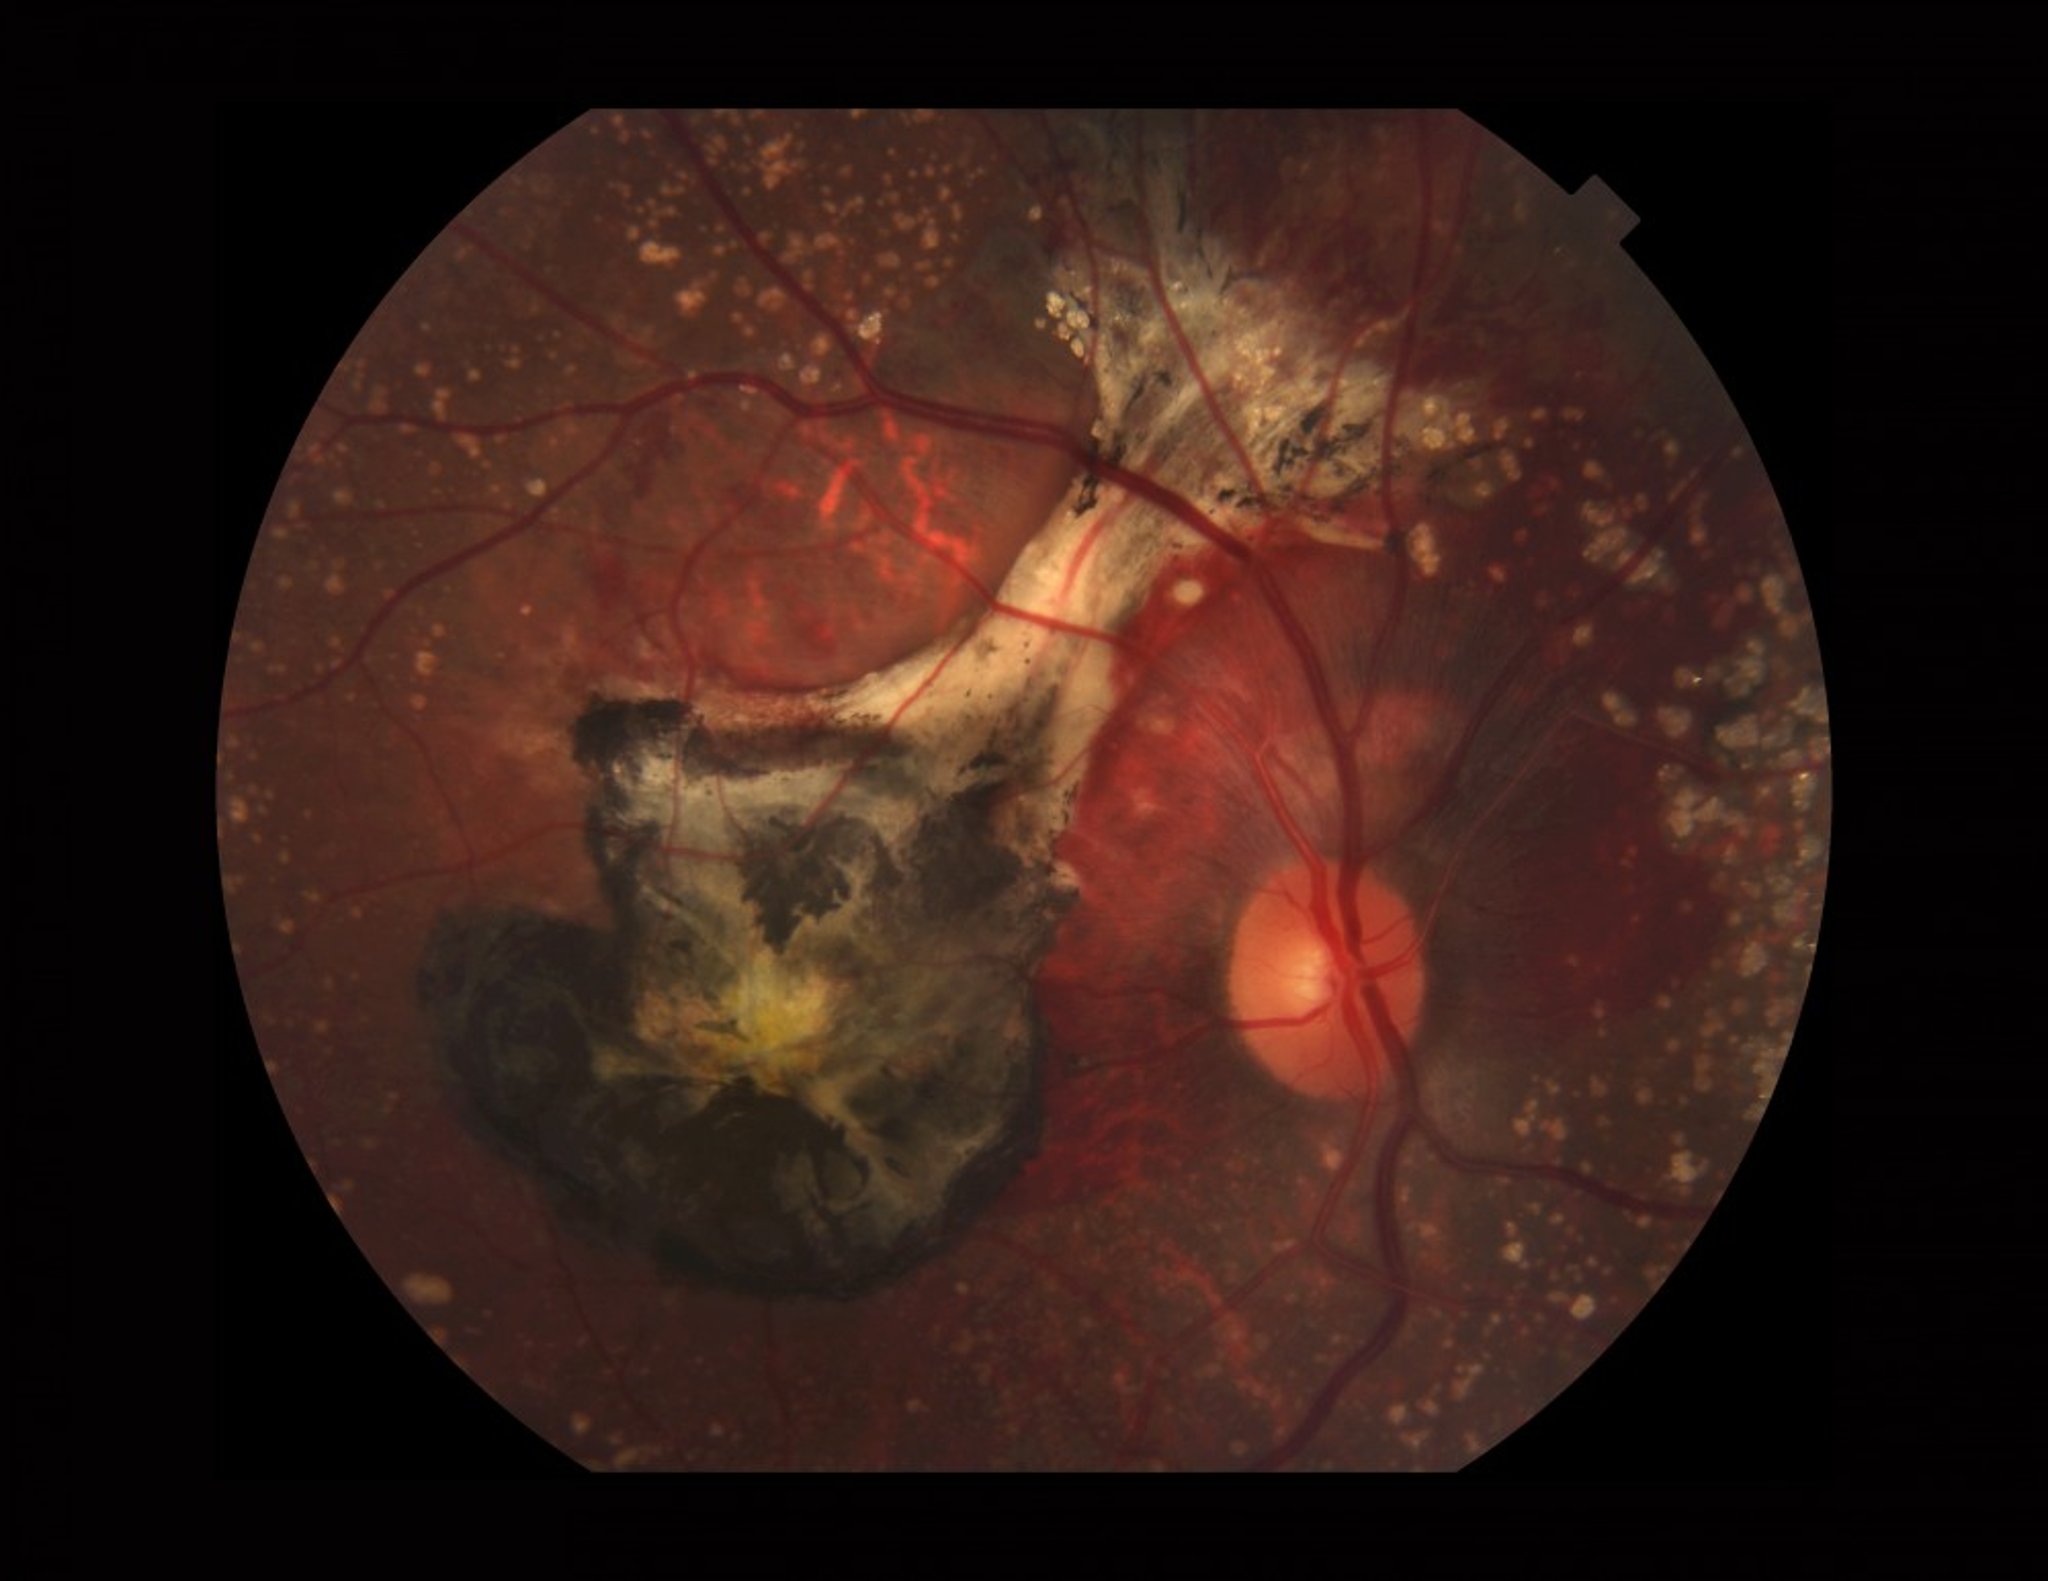

Age-Related Macular Degeneration (Wet)

Photograph of a retina affected by wet AMD. This image shows calcified drusen, subretinal bleeding, a choroidal neovascular membrane (black from old blood and fibrosis), and xanthophyll (yellow) pigment in the macula.

PAUL WHITTEN/SCIENCE PHOTO LIBRARY